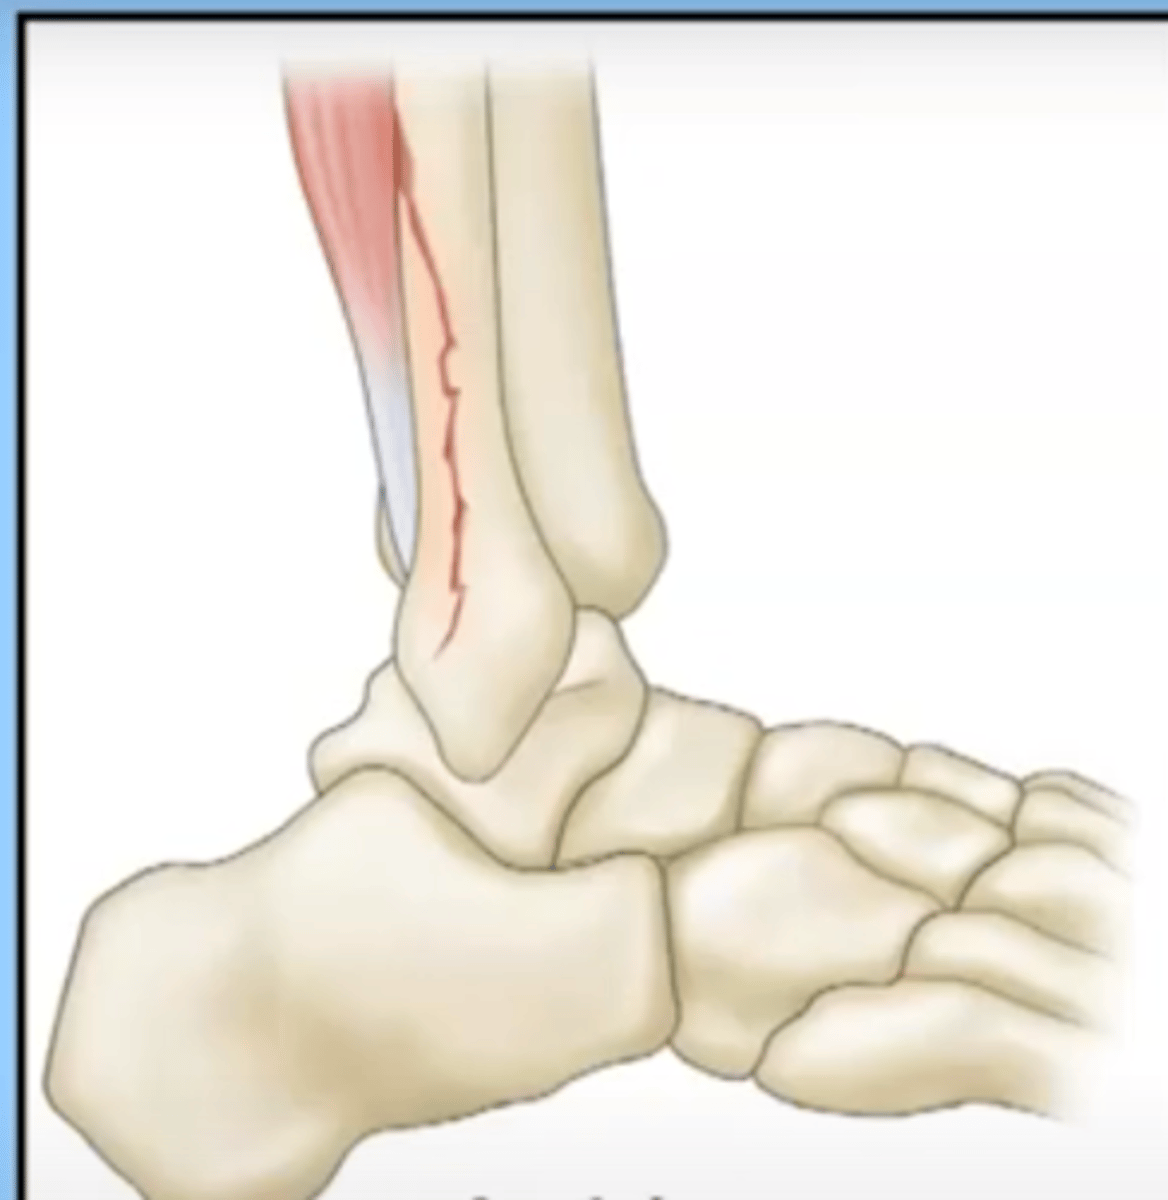

avulsion

a fracture in which a fragment of bone has been pulled away by a tendon and it's attachment